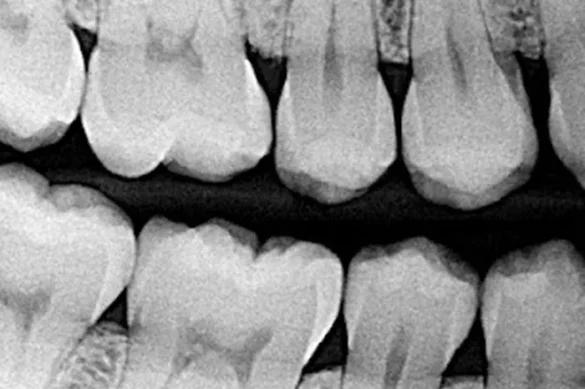

Dental bitewing X-rays are specialised radiographic photos that play a essential position in present day preventive dentistry. When a dentist wishes specific data approximately the areas among enamel and the circumstance of bone surrounding them, bitewing X-rays are regularly the favored diagnostic tool. These photos provide a clear, unique view of the higher and decrease enamel in a unmarried phase of the mouth, mainly focused on the lower back enamel—molars and premolars. Their primary benefit lies of their cappotential to expose troubles invisible to the bare eye at some stage in habitual exams.

A bitewing X-ray is a sort of intraoral radiograph. The call comes from the tab or ‘wing’ that sufferers chew directly to maintain the sensor or movie regular in the mouth. This smart layout guarantees that the X-ray photograph captures each the higher and decrease enamel, focusing in particular on wherein they contact every other—the interproximal areas. These regions are tough to study directly, as they may be hidden with the aid of using the neighboring teeth surfaces. By highlighting those areas, bitewings assist dentists discover problems which includes cavities, bone loss, and the fitness of dental restorations.

When a bitewing X-ray is taken, the affected person bites down at the wing-formed tab, commonly positioned on every aspect of the mouth for entire insurance of the posterior enamel. The X-ray sensor or movie facts the crowns of the enamel and a part of the helping bone. Unlike full-mouth or panoramic X-rays, bitewings awareness simplest at the enamel and bone of a small phase, presenting high-decision details. Modern bitewing X-rays are usually virtual and require simplest a minimum quantity of radiation, making them secure and efficient.

Bitewing X-rays are designed to expose the crowns of the higher and decrease lower back tooth, the areas among tooth, and a phase of the assisting bone. They are quality for locating cavities and monitoring bone loss.